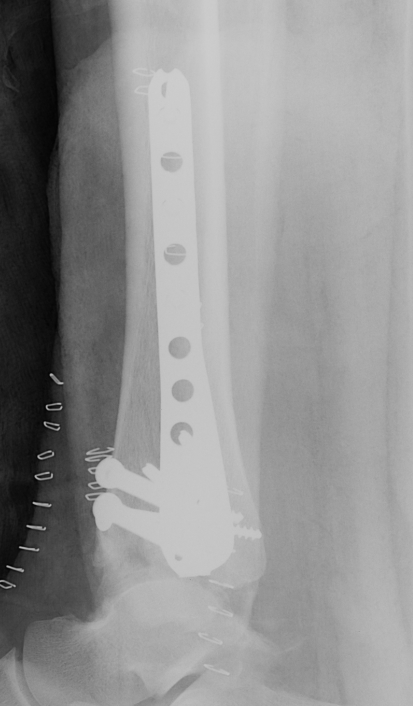

ORIF with Plates

Principle

Restore articular surface

Fix articular surface to metaphysis

Anatomical Plates

Medial plateAnterolateral plate

Synthes medial plate                               Synthes anterolateral plate

Tibial Plafond CT AxialTibial Plafond CT SagittalPlafondTibial Plafond ORIF APTibial Plafond ORIF Lateral